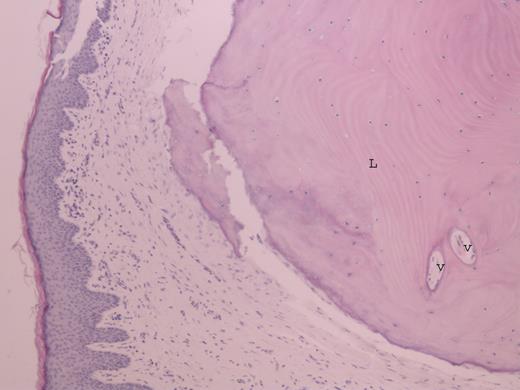

At surgery, transmeatal exicision of the EAC osteoma revealed an underlying cholesteatoma that has caused bony erosion of the inferior canal wall (Fig. 2) and formed a fistulous connection to the overlying neck skin (Fig. 3). The post-aural sinus and fistula were excised through a post-auricular incision. A cortical mastoidectomy was performed to explore the mastoid cavity, which was found to be disease free. The temporalis fascia was harvested and used to reconstruct the inferior canal wall defect. Histopathologic examination of the excised tissues confirmed the synchronous dual pathology involving the EAC (Figs 4 and 5).

Photomicrograph of osteoma within the skin of external auditory canal showing lamellar bone (L) and fibrovascular channel (V) (H&E ×20).